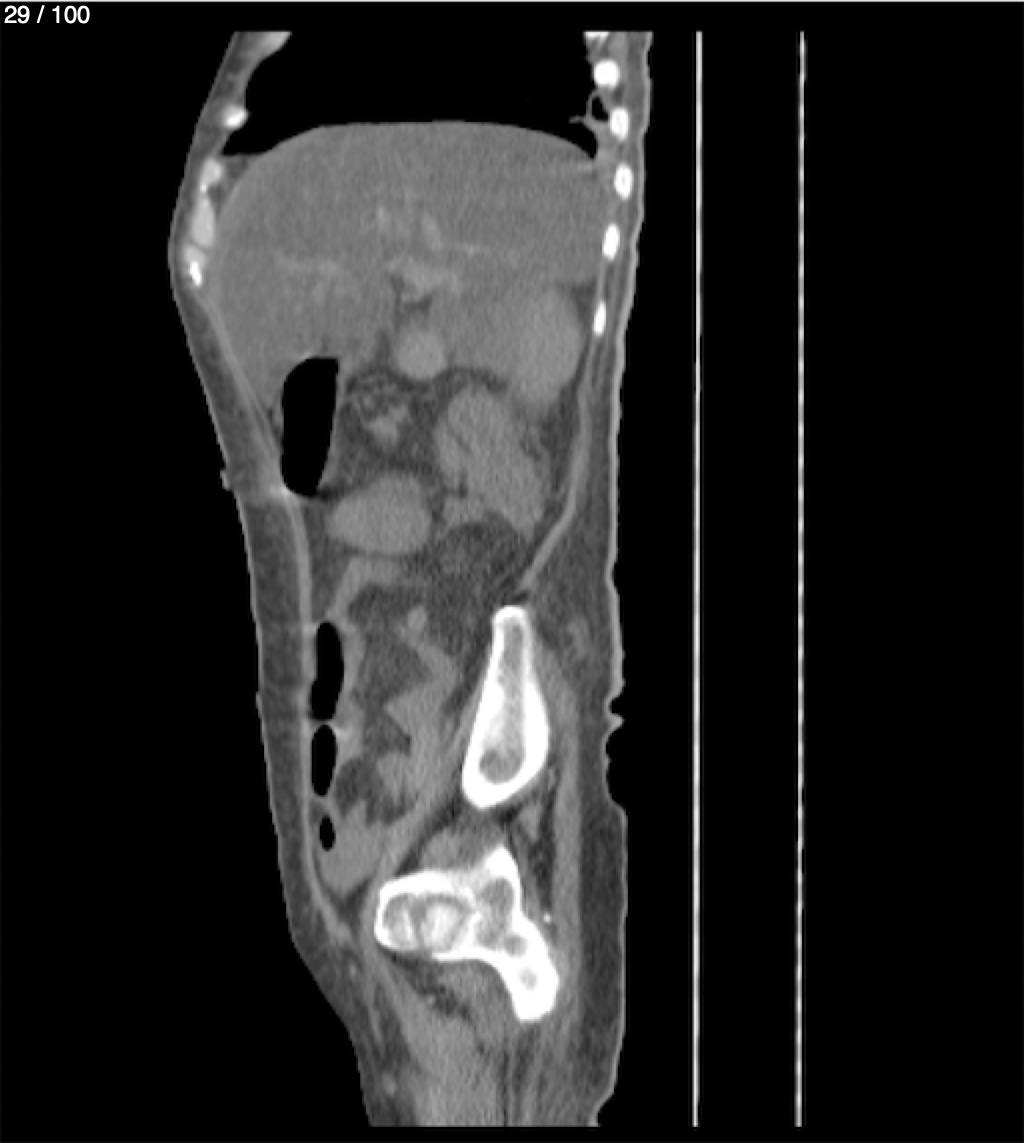

Hilda Geronimo Mendez 60A - T.C Abdomen Simple